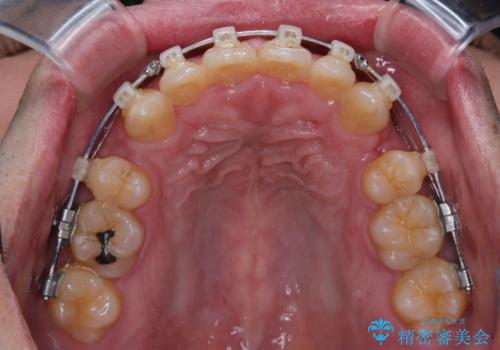

- 矯正装置

- クリアブラケット

- 治療期間

- 2年3ヶ月